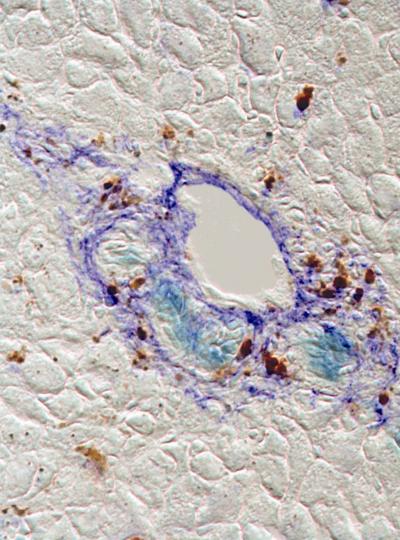

PHILADELPHIA - A novel protein marker has been found that identifies rare adult liver stem cells, whose ability to regenerate injured liver tissue has the potential for cell-replacement therapy. For the first time, researchers at the University of Pennsylvania School of Medicine led by Linda Greenbaum, MD, Assistant Professor of Medicine in the Division of Gastroenterology, have demonstrated that cells expressing the marker can differentiate into both liver cells and cells that line the bile duct.

For chronic injury, the liver uses a back-up system that stimulates stem cells to proliferate and eventually differentiate into new liver cells. Greenbaum and colleagues found that these dual-potential stem cells can be identified and potentially isolated from other liver cells because they uniquely express the protein Foxl1. The team showed that in two mice models of liver injury, stem cells and their descendents were marked by the expression of FoxL1. The researchers propose to use this marker to isolate the Foxl1-bearing stem cells and transplant them back into damaged livers to restore function.